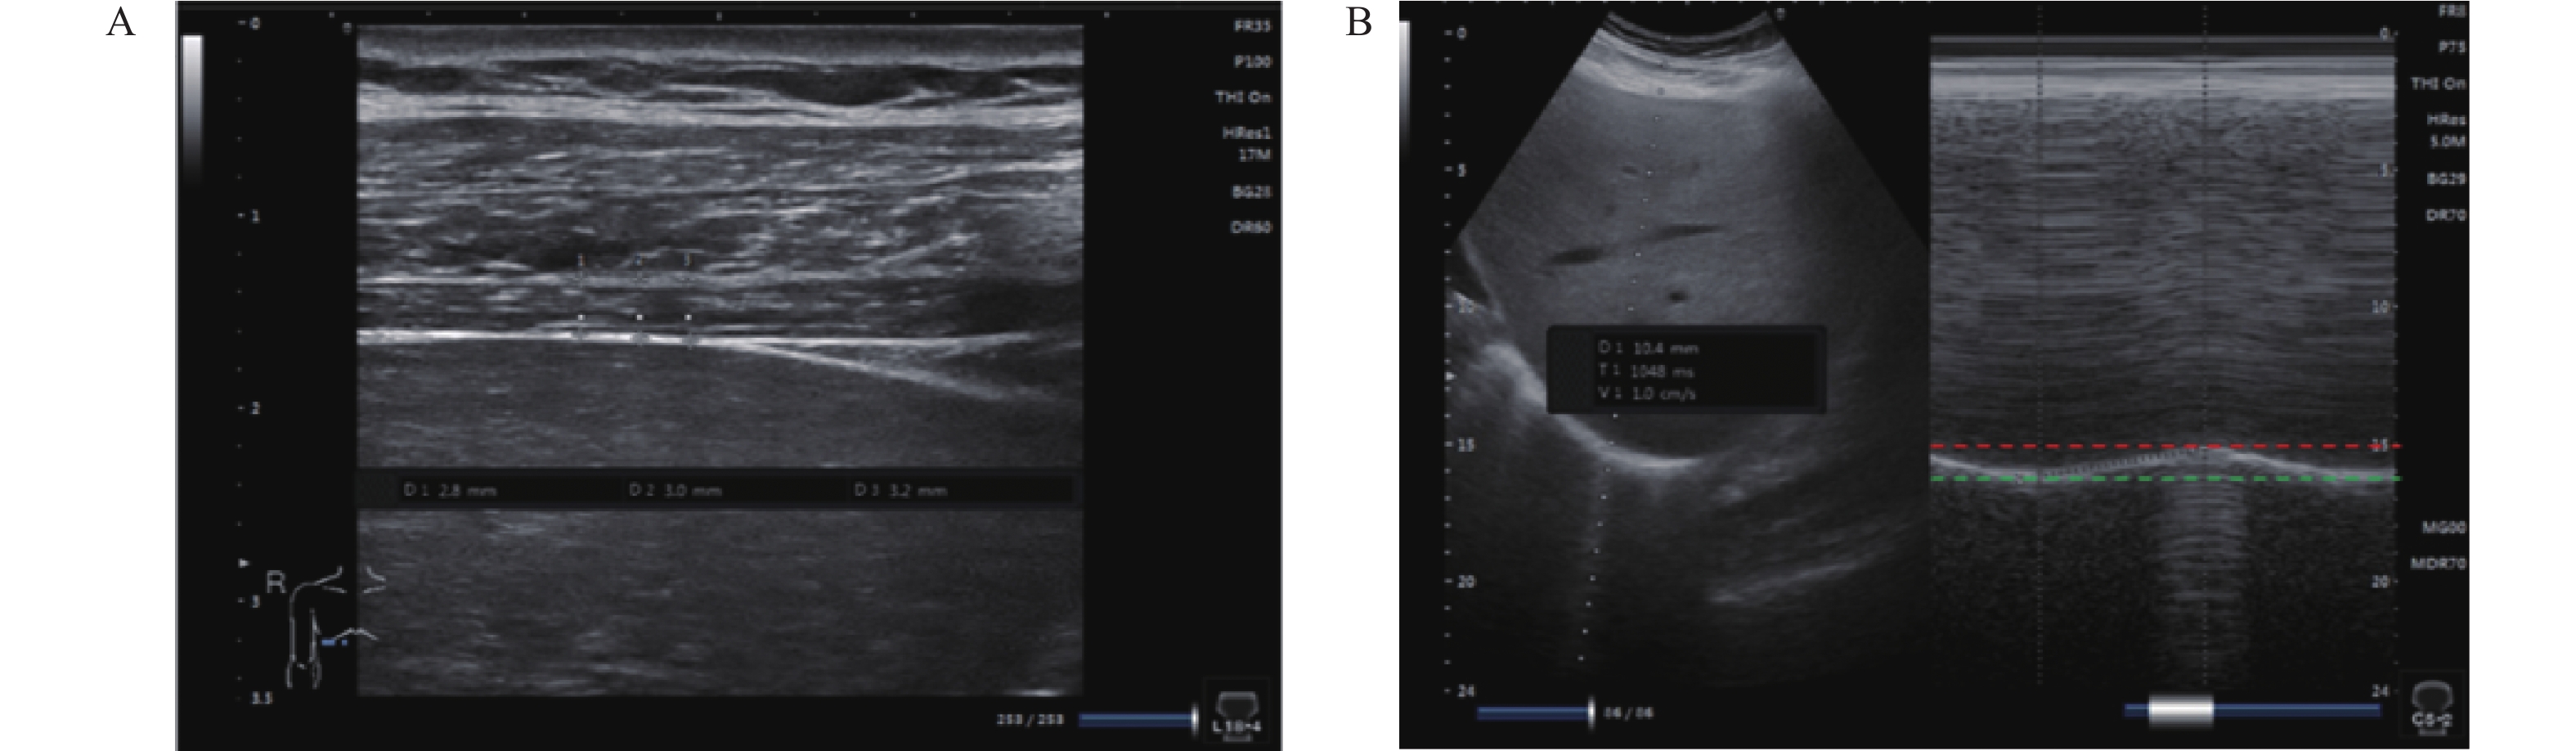

子宫动脉血流联合血清因子对孕中期子痫预后价值

雷蕊艳, 郝慧敏, 王佩颖, 孙慧, 张丽

摘要(403) HTML(372) PDF (109)

摘要:

目的  探讨子宫动脉血流多普勒超声联合血清细胞因子信号抑制因子 3(suppressor of cytokine signaling 3,SOCS-3)、纤维蛋白3(Fibulin-3)在孕中期子痫前期孕妇妊娠结局预测中的价值。  方法  采用回顾性分析法,采集西北妇女儿童医院医学超声中心在2022年1月-2024年12月期间接收的123例孕中期子痫前期孕妇作为病例组;另择取105例健康常规检查孕中期孕妇作为正常组,采用彩色多普勒超声检测子宫动脉血流参数,包括搏动指数(pulsatility index,PI)、阻力指数(resistance index,RI)和收缩期峰值流速与舒张末期流速比值(systolic peak velocity to end-diastolic velocity ratio,S/D);运用酶联免疫吸附试验(enzyme-linked immunosorbent assay,ELISA)检测血清 SOCS-3、Fibulin-3 水平。通过统计学分析评估各指标单独及联合检测对子痫前期妊娠结局的预测效能,计算曲线下面积(area under the curve,AUC)、敏感性和特异性。  结果  病例组孕妇子宫动脉血流 PI、RI、S/D 值及 Fibulin-3 水平均高于正常组(P < 0.05),血清 SOCS-3 水平显著低于正常组(P < 0.05)。妊娠中期子痫前期孕妇中,共发生早产 3 例、胎儿生长受限 5 例、胎盘早剥 10 例、子痫 7 例、产后出血 10 例,不良妊娠结局合计 35 例。单因素分析显示,PI、RI、S/D 值及血清 SOCS-3、Fibulin-3 水平均为妊娠不良结局的影响因素(P < 0.05);Logistic 回归分析证实,Fibulin-3 升高、RI 升高、S/D 值升高、SOCS-3降低、PI 升高是不良妊娠结局的独立危险因素(P < 0.05)。构建联合预测模型(回归方程:Fibulin-3×4.767+RI×1.735+S/D 值×2.286-SOCS-3×10.402+PI×1.044),其 ROC 曲线下面积(AUC)为 0.998,特异度 96.59%,敏感度 100.00%,显著优于各单项指标(Fibulin-3 AUC 0.996、RI AUC 0.977、S/D 值 AUC 0.877、SOCS-3 AUC 0.914、PI AUC 0.794,P < 0.05)。  结论  子宫动脉血流参数与血清 SOCS-3、Fibulin-3 水平相结合,能显著提升孕中期子痫前期孕妇不良妊娠结局的预测准确性。